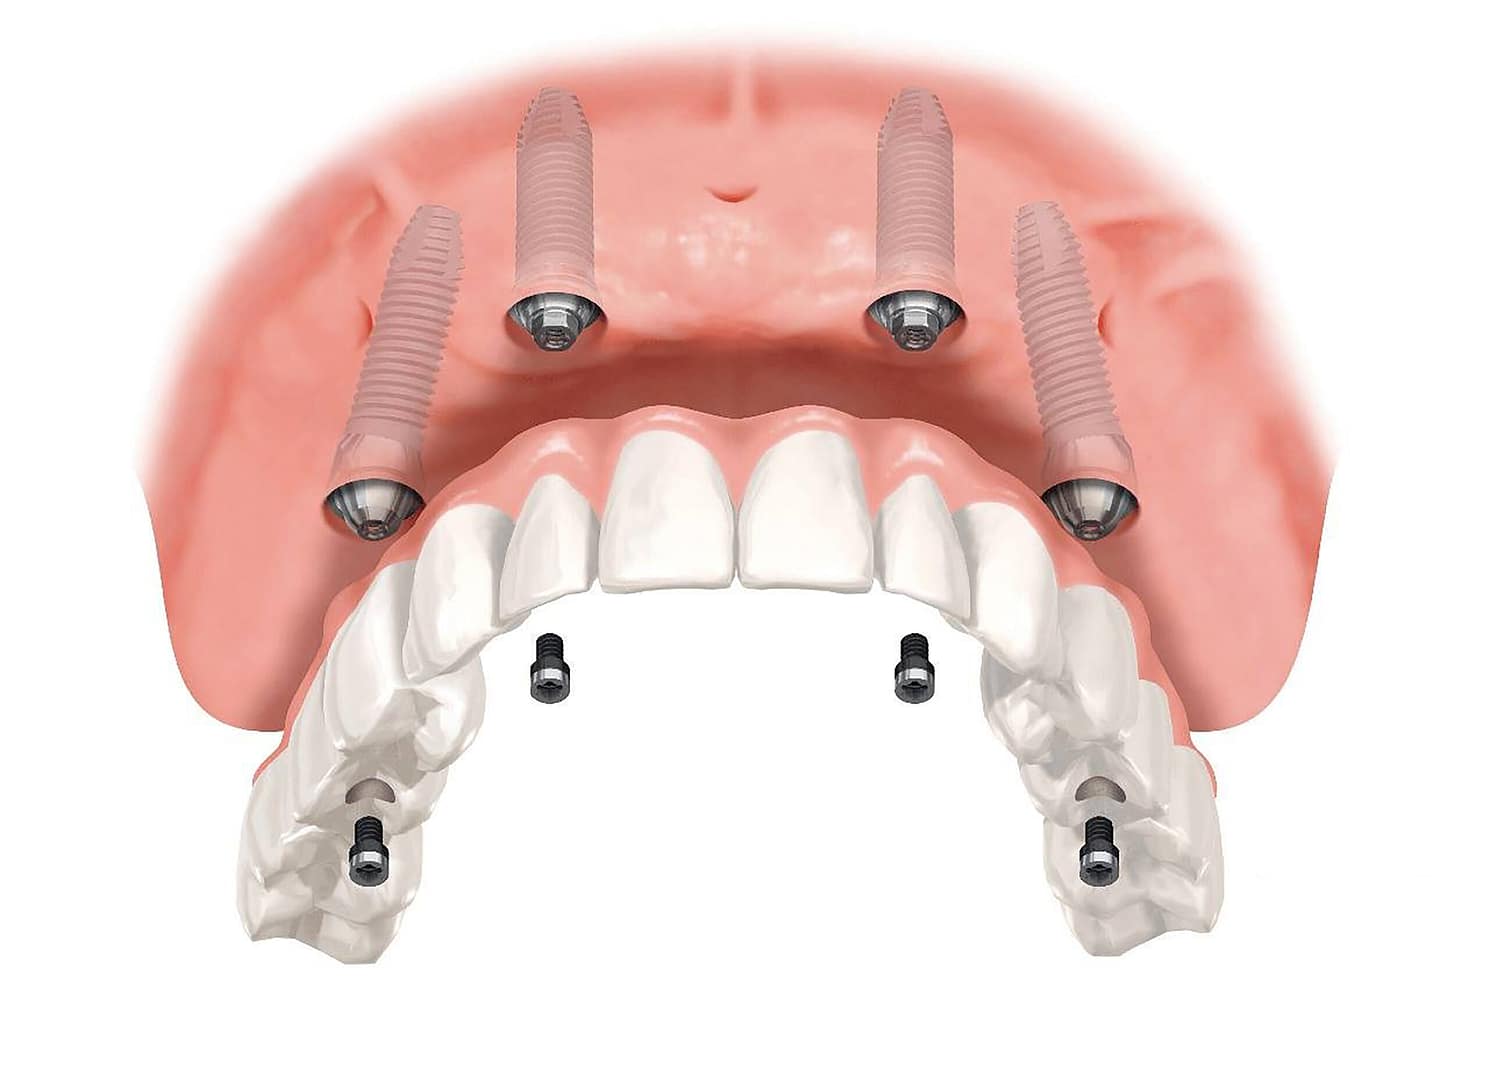

La osteointegración es, en esencia, la conexión estructural y funcional directa entre la superficie de un implante artificial y el hueso vivo del paciente, sin la interposición de tejido blando.

- La osteointegración es, en esencia, la conexión estructural y funcional directa entre la superficie de un implante artificial y el hueso vivo del paciente, sin la interposición de tejido blando.

- Cuando el implante se coloca en el hueso, las células óseas (osteoblastos) migran y comienzan a depositar nuevo hueso directamente sobre la superficie rugosa y porosa del titanio.